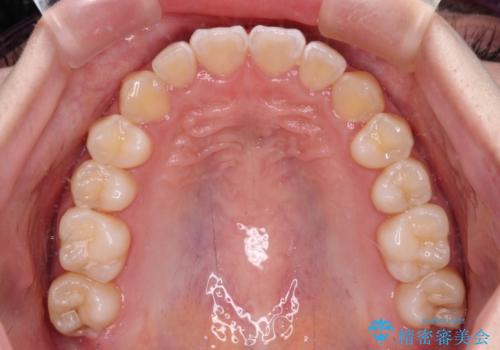

外側を向いていた奥歯は比較的早い時期に歯列に収まり、咬み合わせも磨きやすさも改善することができました。

歯列は元々悪くなかったので、1年ほどで治療を終えることができました。